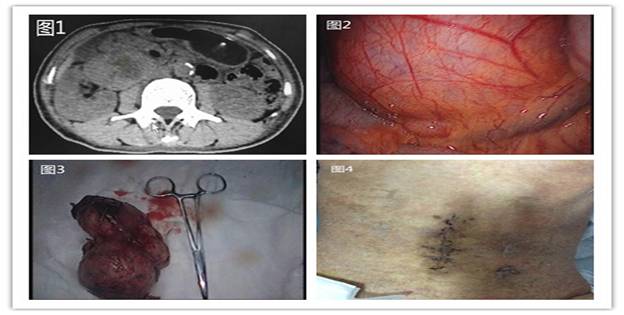

據(jù)悉,59歲的患者羅阿姨在7-8年前就已發(fā)現(xiàn)腹腔內(nèi)一腫塊,當(dāng)時(shí)僅“核桃”大小,因沒有任何不適,所以也就沒引起重視。直到近日,因“糖尿病、皮膚濕疹”入住我院內(nèi)分泌科,查體顯示,右下腹可捫及一約6cm*5cm大小包塊,邊界清,無明顯壓痛,全腹CT檢查發(fā)現(xiàn)其右側(cè)中腹部可見一約11cm*6cm*6cm巨大混雜密度包塊,周圍臟器受壓明顯(圖1)。為求外科治療,轉(zhuǎn)入胃腸外科。經(jīng)過仔細(xì)分析病例、閱片,發(fā)現(xiàn)該患者腹腔內(nèi)的巨大腫瘤位于腹膜后,已累及腹腔重要血管、神經(jīng)及臟器,手術(shù)難度較大。結(jié)合患者既往糖尿病多年,血糖控制差,若行傳統(tǒng)開腹手術(shù),術(shù)后切口感染、愈合又是一難題;若不進(jìn)行手術(shù),巨大腫瘤將有繼續(xù)壓迫臟器、甚至破裂可能,以致威脅生命。為此,在譚曙光主任的帶領(lǐng)下,全科人員反復(fù)研究病例,考慮腹腔鏡手術(shù)具有創(chuàng)傷小、恢復(fù)快、鏡下視野清晰、安全可靠等優(yōu)點(diǎn),決定行腹腔鏡微創(chuàng)手術(shù)。

術(shù)中探查發(fā)現(xiàn),腫塊位于右側(cè)結(jié)腸旁溝、右腎下極與十二指腸降部間隙(圖2)。由于腫塊較大,術(shù)中盡量游離周圍臟器、血管,進(jìn)而形成“圍攻式”完整剝離腫塊,術(shù)中失血約20ml。經(jīng)過約2個(gè)小時(shí)的努力,埋在患者體內(nèi)的這枚“定時(shí)炸彈”被順利摘除(圖3)。術(shù)后患者腹部切口愈合良好(圖4)。